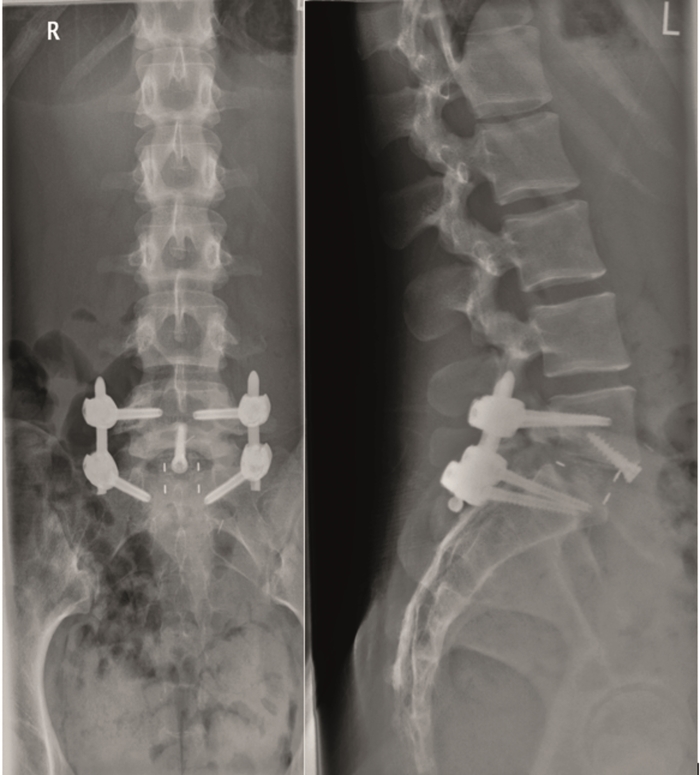

From six months postoperatively, leg discomfort decreased. Within an additional four months, pain disappeared completely and both foot and hip weakness recovered. The back pain persists to a certain extent but is not impedingthe patient in her daily activities. The x-ray taken 10 months after the anterior revision surgery revealed a complete and solid fusion on both levels (Fig 8). This is confirmed by the appearance of dense bone in the radiolucentcage.